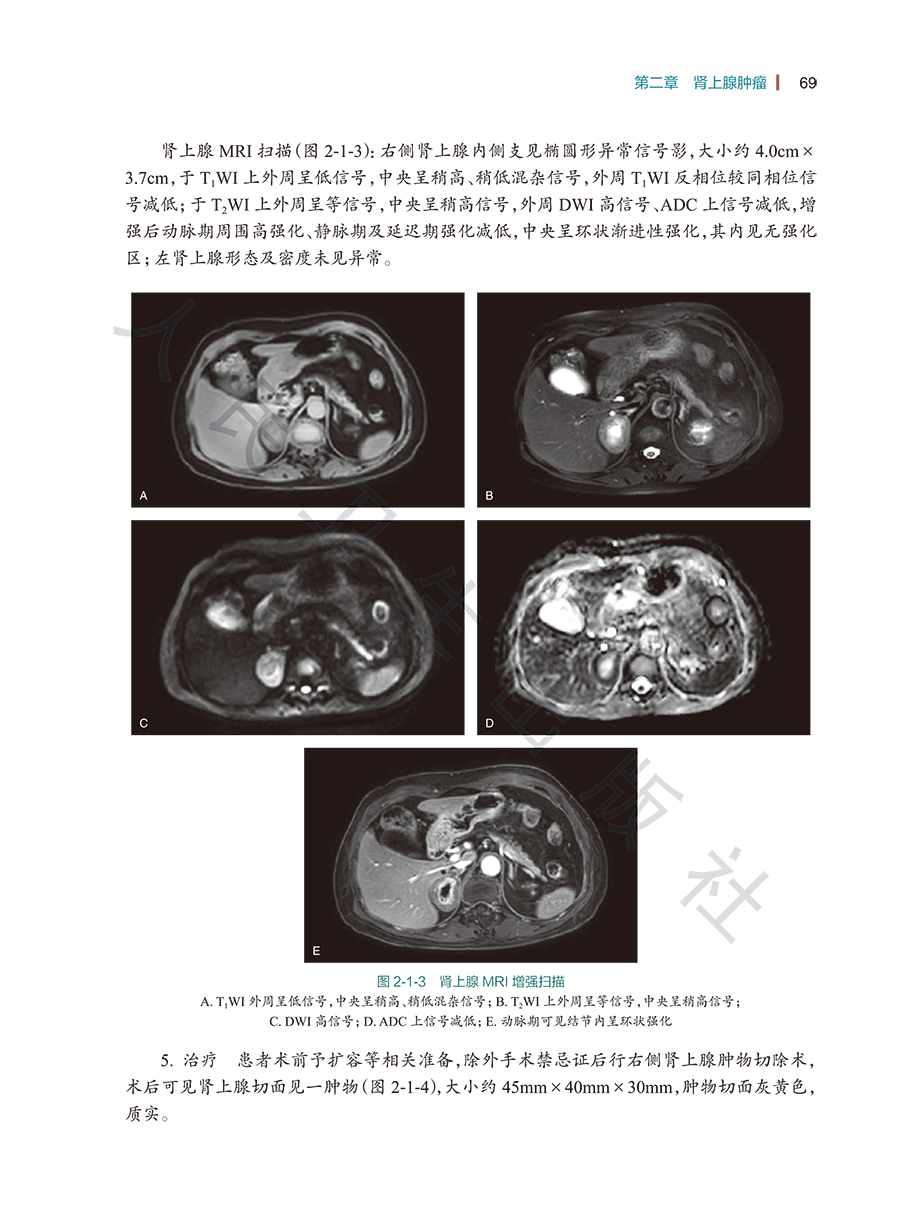

第一节嗜铬细胞瘤/67